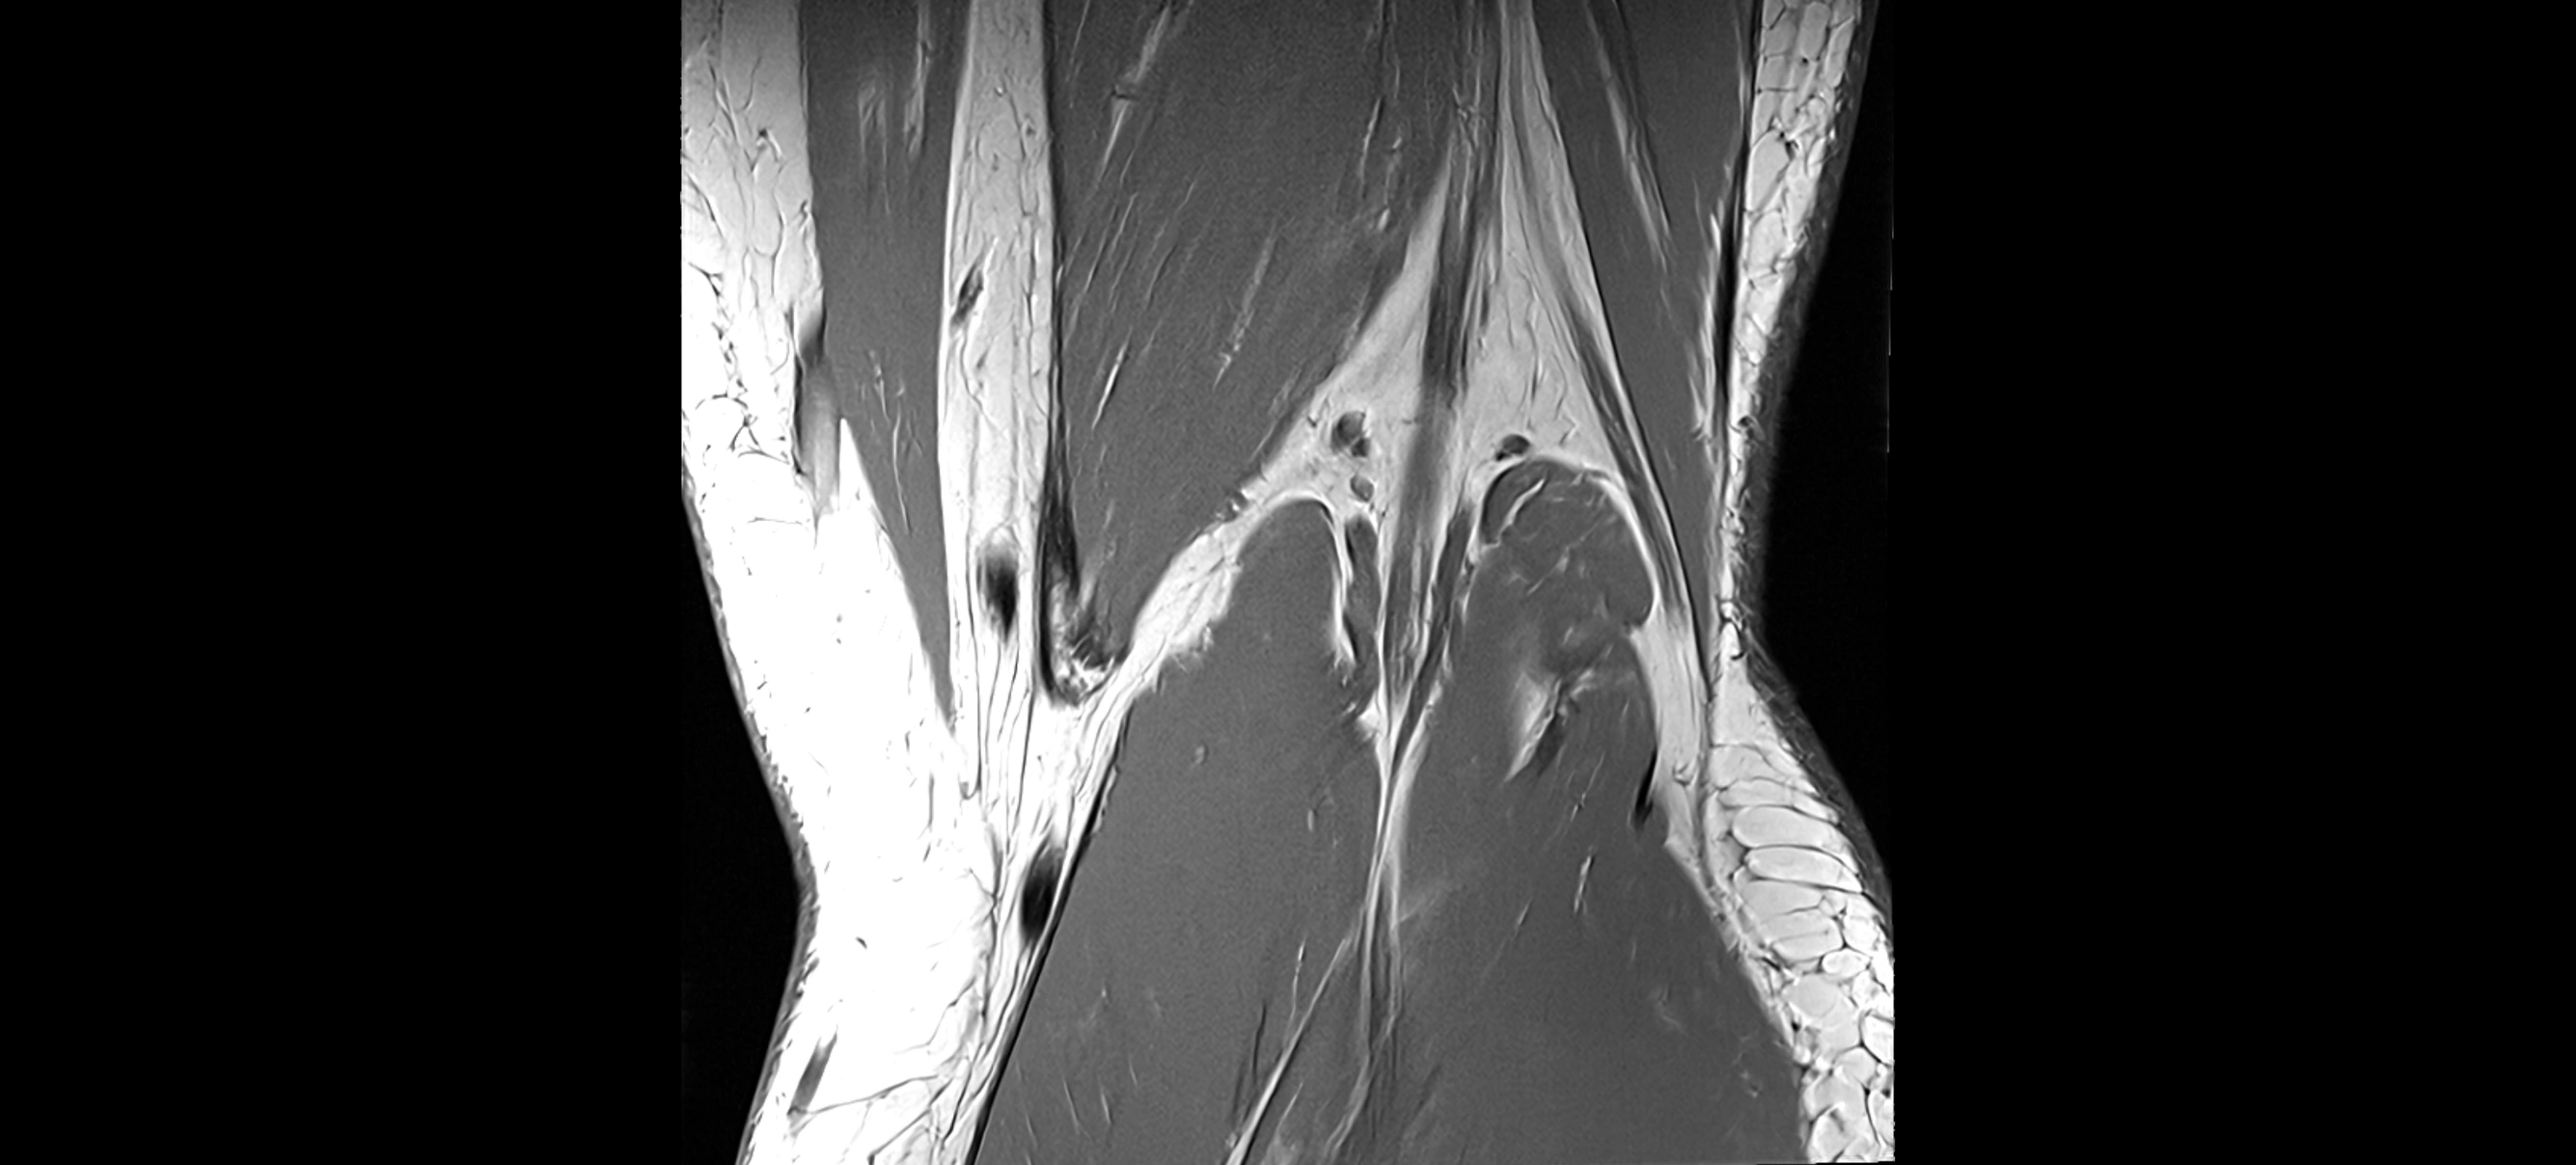

MRI Appearance

T1-weighted images:

• Normal ACL appears as a low-signal band-like structure crossing the intercondylar notch

• Surrounded by intermediate signal synovial fluid and fat planes

T2-weighted images:

• Normal ACL remains low signal

• Partial or complete tears appear as discontinuity, increased signal, or fiber laxity

MRI images

image